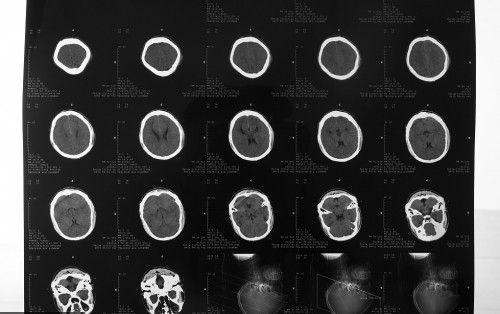

我常常为生意忙到晚上十一二点,常常导出奔走,家人都说我太劳累了,我也知道自己很累,但我还有两个孩子,所以我不得不努力。一个作为母亲为了孩子的心情,大概也只有同样升为人母的女性才能了解。在我们自己的打拼下,日子开始慢慢变好,可是我却被查出患了肺癌。